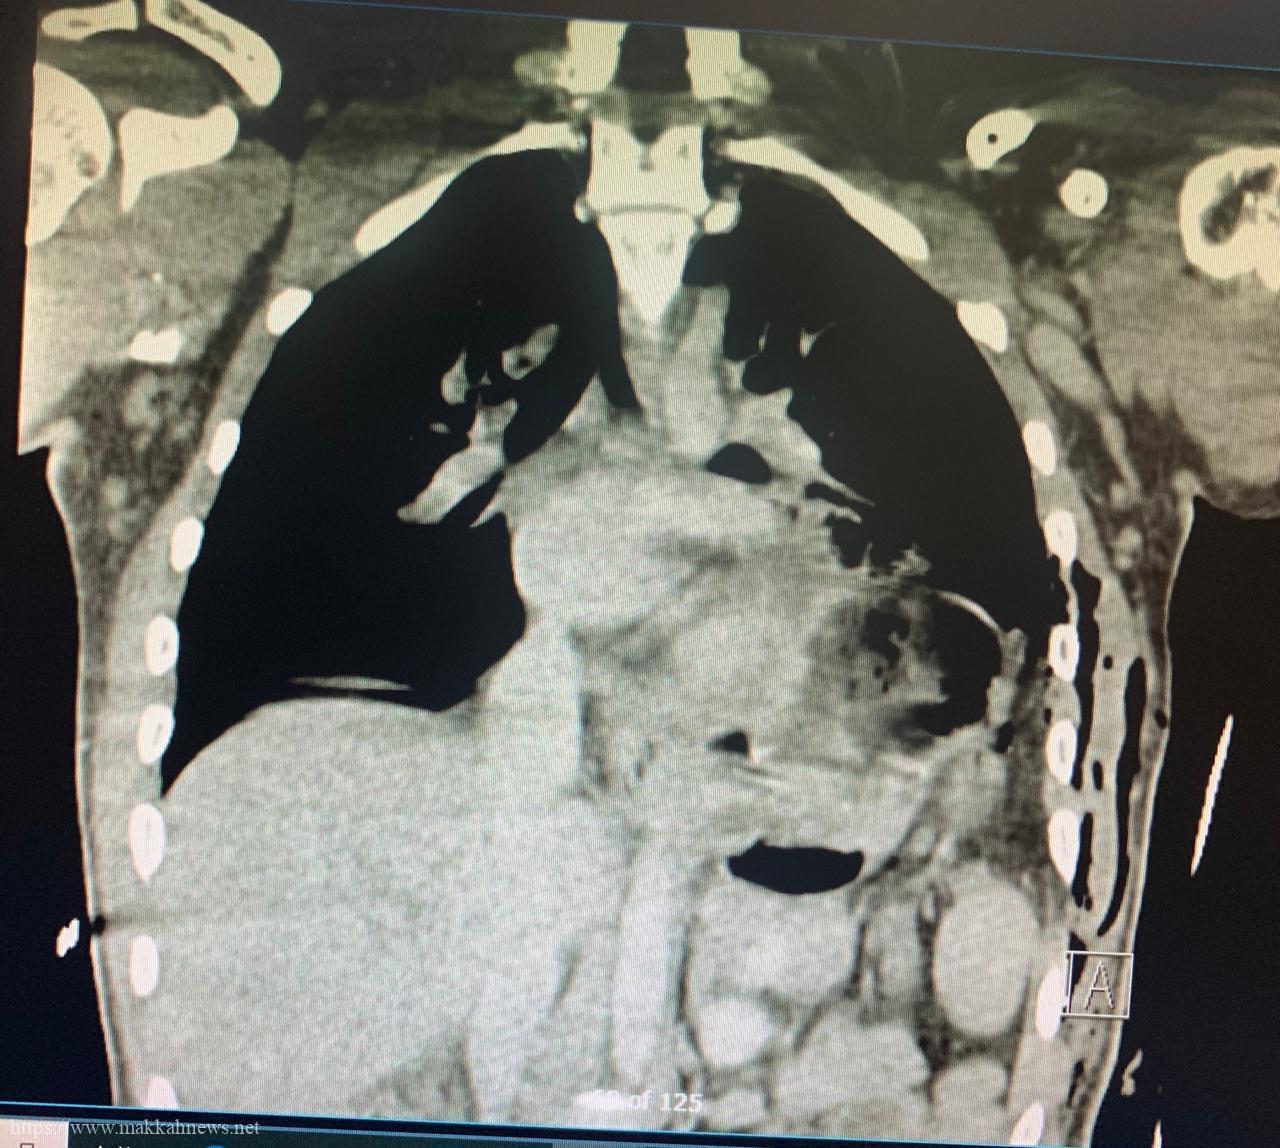

عملية عاجلةوحرجة بطبية مكه لشاب اثرإخترق اسياخ حديدة بجسده

الاتصال المؤسسي – مكه أنقذت العناية الالهية ثم تدخل جراحي عاجل لفريق طبي متخصص من مركز الجراحات التخصصية بمدينة الملك…